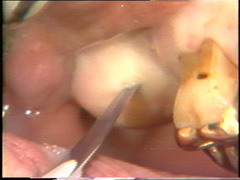

La incisión inicial se empieza alrededor de 10-15 mm distal del último diente hasta la línea media del proceso alveolar. Esto se hace para evitar el cierre del colgajo que está en la proximidad de la furcación que se abre en distal del primer molar. La incisión se realiza con una presión tal para llegar a hacer contacto con el hueso. |

La incisión es entonces continuada en bucal siguiendo la línea del margen gingival pero ubicando el corte en 1 a 1,5 mm hacia apical. La incisión debe partir de coronal del hueso alveolar en la proximidad del diente. En el segundo premolar el bolsillo está muy profundo y aquí la incisión se ensancha para generar reducción de la bolsa que luego es reemplazado por el colgajo. |